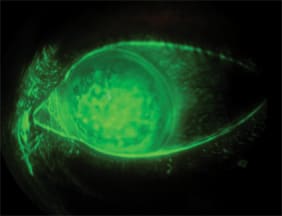

This photograph shows a bandage soft contact lens on the left eye of a patient who has bullous keratopathy. The patient unfortunately experienced an acute angle closure attack as an infant and has never had useful vision with the affected eye. His previously high eye pressure and inflammation damaged his endothelium and he developed mild bullous keratopathy. He had been using Cosopt (Merck & Co.) b.i.d. OS and Muro 128 (Bausch & Lomb) drops OS as needed.

The patient had recently complained of increased pain/irritation in his left eye. Slit lamp examination showed moderate bullous keratopathy OS. He trialed a CIBA Vision Night & Day bandage contact lens with an 8.6mm base curve, −0.75D. He wore the lens on a daily wear basis and used Clear Care (CIBA) as a care system. The patient returned in two weeks reporting significantly improved comfort, so we prescribed the Night & Day lens for monthly replacement as a bandage lens.